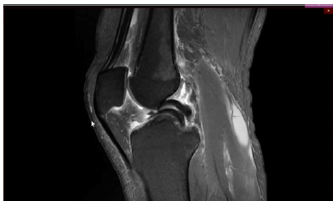

Um paciente de 19 anos de idade sofreu entorse do joelho direito durante agachamento em partida de futebol. Foi retirado do campo e queixando-se de dor na face interna do joelho. Foi levado ao hospital mais próximo e, ao ser examinado, percebeu que não conseguia estender completamente o joelho. Não conseguia flexionar totalmente o joelho também. Notaram-se ainda, edema e o sinal da tecla.

Enunciado 4335244-1

Considere que, no caso clínico descrito, foi realizado o exame complementar, conforme apresentado. Essa figura mostra